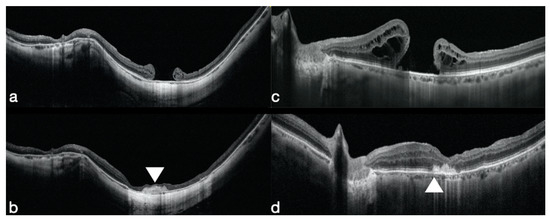

3.1. Macular Holes that Failed to Close

- Rizzo, S.; Caporossi, T.; Tartaro, R.; Finocchio, L.; Franco, F.; Barca, F.; Giansanti, F. A Human Amniotic Membrane Plug to Promote Retinal Breaks Repair and Recurrent Macular Hole Closure. Retina 2019, 39 (Suppl. 1), S95–S103. [Google Scholar] [CrossRef]

- Kang, S.W.; Ahn, K.; Ham, D.I. Types of macular hole closure and their clinical implications. Br. J. Ophthalmol. 2003, 87, 1015–1019. [Google Scholar] [CrossRef]